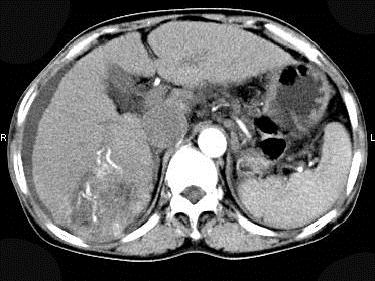

问题 女性,55岁,曾患乙肝,肝硬化多年,右上腹胀痛1月余,CT检查如图所示,最可能的诊断是()

选项 A.肝硬化腹水、下腔静脉血栓形成 B.肝硬化腹水、胆管细胞癌 C.肝硬化腹水、肝癌并下腔静脉癌栓 D.肝硬化腹水、肝脓肿 E.肝硬化腹水、肝血管瘤

答案 C